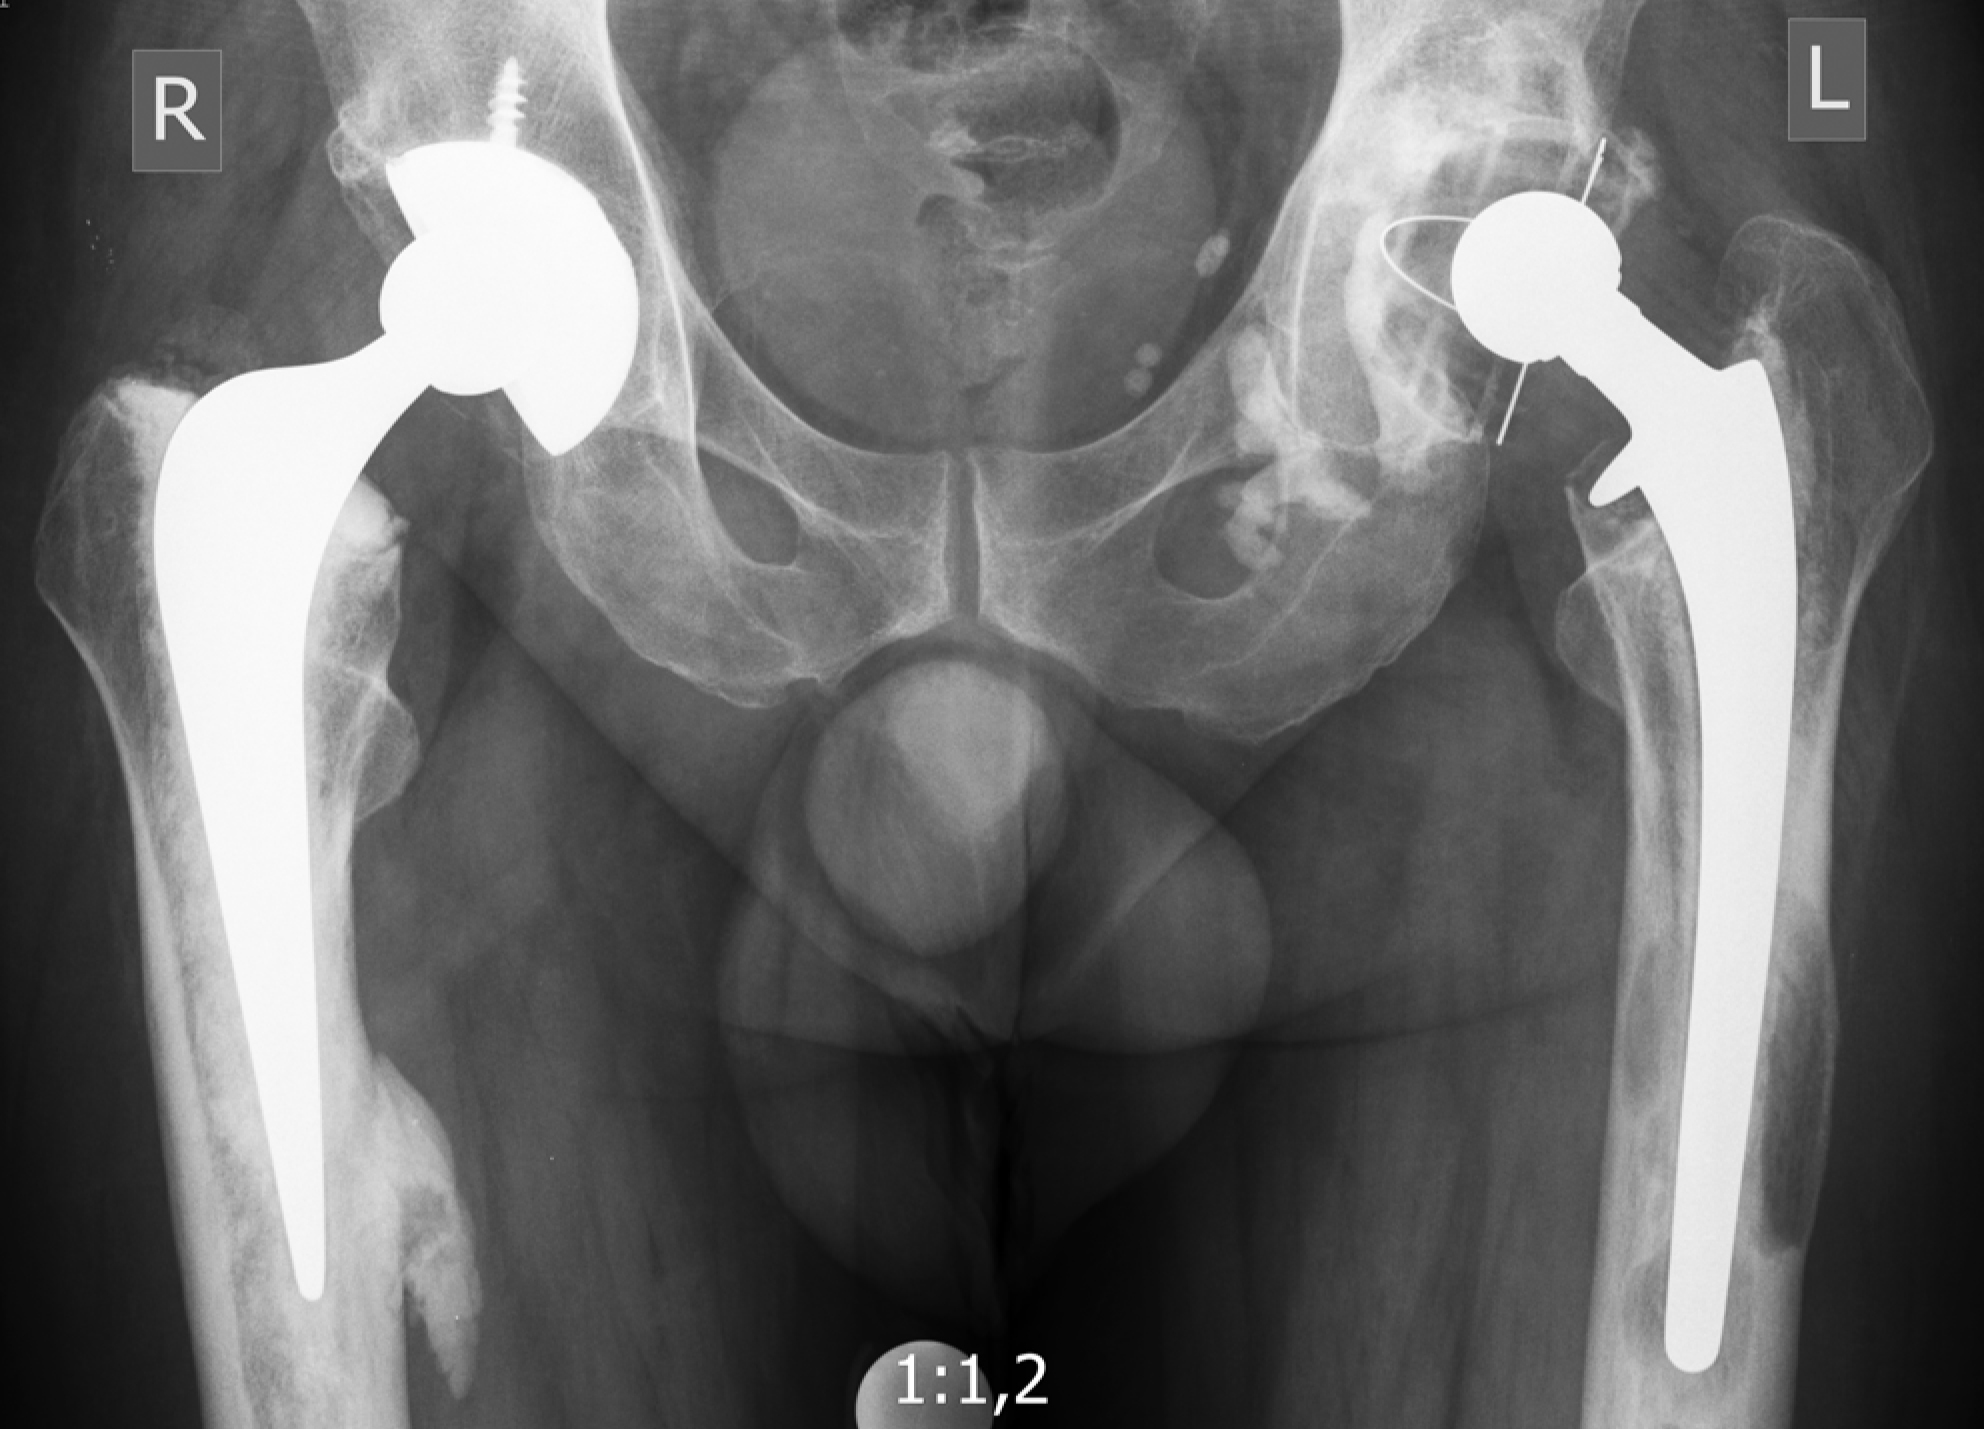

Уплотнение материала и уменьшение его объема при увеличении числа циклов нагрузки можно пояснить клиническими примерами. Проведена оценка результатов рентгенологического исследования в динамике у пациентки 59 лет (пациент 1), перенесшей двухэтапное ревизионное эндопротезирование по поводу инфицированной нестабильности компонентов эндопротеза с использованием ИКП на заключительном этапе (рис. 6). Для анализа динамики миграции тазового компонента выбраны обзорные рентгенограммы таза, полученные непосредственно после операции, через 3 года после оперативного вмешательства и на последнем контрольном осмотре через 7 лет (рис. 7). Абсолютные значения представлены в таблице 3.

Проведен анализ обзорных рентгенограмм таза пациента 53 лет (пациент 2), перенесшего ревизионное эндопротезирование левого тазобедренного сустава по поводу асептического расшатывания компонентов эндопротеза тазобедренного сустава с применением ИКП на тазовом и бедренном сегментах (рис. 8).

Для оценки рентгенологической динамики выбраны снимки, выполненные непосредственно после операции, через 1 год и на последнем контрольном осмотре через 5 лет с момента операции, на который пациент явился с жалобами на боли в области левого тазобедренного сустава (рис. 9). Функциональная оценка по модифицированной шкале HHS на момент последнего осмотра составила 53 балла. При оценке рентгенограмм в динамике после ревизионного эндопротезирования отмечается постепенное смещение центра ротации краниально до 14,9 мм и латерально до 9,5 мм, увеличение инклинации и изменение антеверсии тазового компонента (табл. 4). Несмотря на отсутствие рентгенологических линий просветления на границе интерфейсов данная миграция тазового компонента в совокупности с болевым синдромом была расценена как расшатывание тазового компонента.